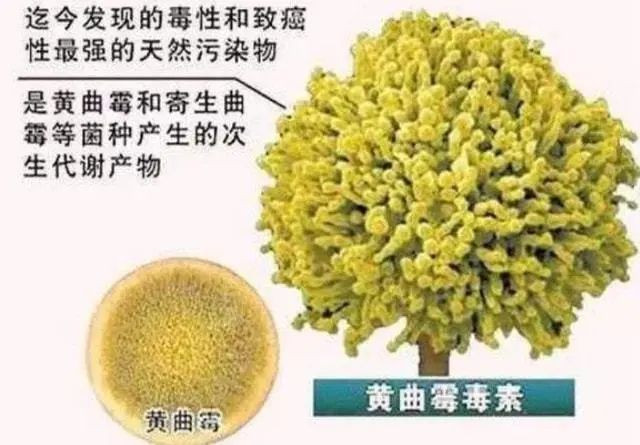

此前,许多报道都指出,过于节俭的饮食习惯容易诱发肝癌而摄入黄曲霉毒素是许许多多华人家庭的饮食习惯危机。

徐阿姨会将看似晒干的花椒直接收起来,所以有一些花椒出现受潮、发霉的现象。事后医生表示这是由于食用发霉的花椒时间久了,导致身体摄入过多的黄曲霉毒素,才诱发了癌症。

但随着科学的发展,现在越来越多的证据表明:发了霉的东西一丁点都碰不得!

在小鼠的饲料中添加0.04%~1%的黄樟素(天然香料里的致癌因素),只需要短短150天到2年,可诱导小鼠产生肝癌。

若多用这些香料调味品(黄樟素),可导致人体细胞畸变,日积月累下导致肿瘤的形成。

大家都知道砒霜含有剧毒,但是一定剂量的毒性竟是砒霜的68倍,氰化钾的10倍。

世界卫生组织国际癌症研究机构发布的部分致癌物清单中也有它的身影。